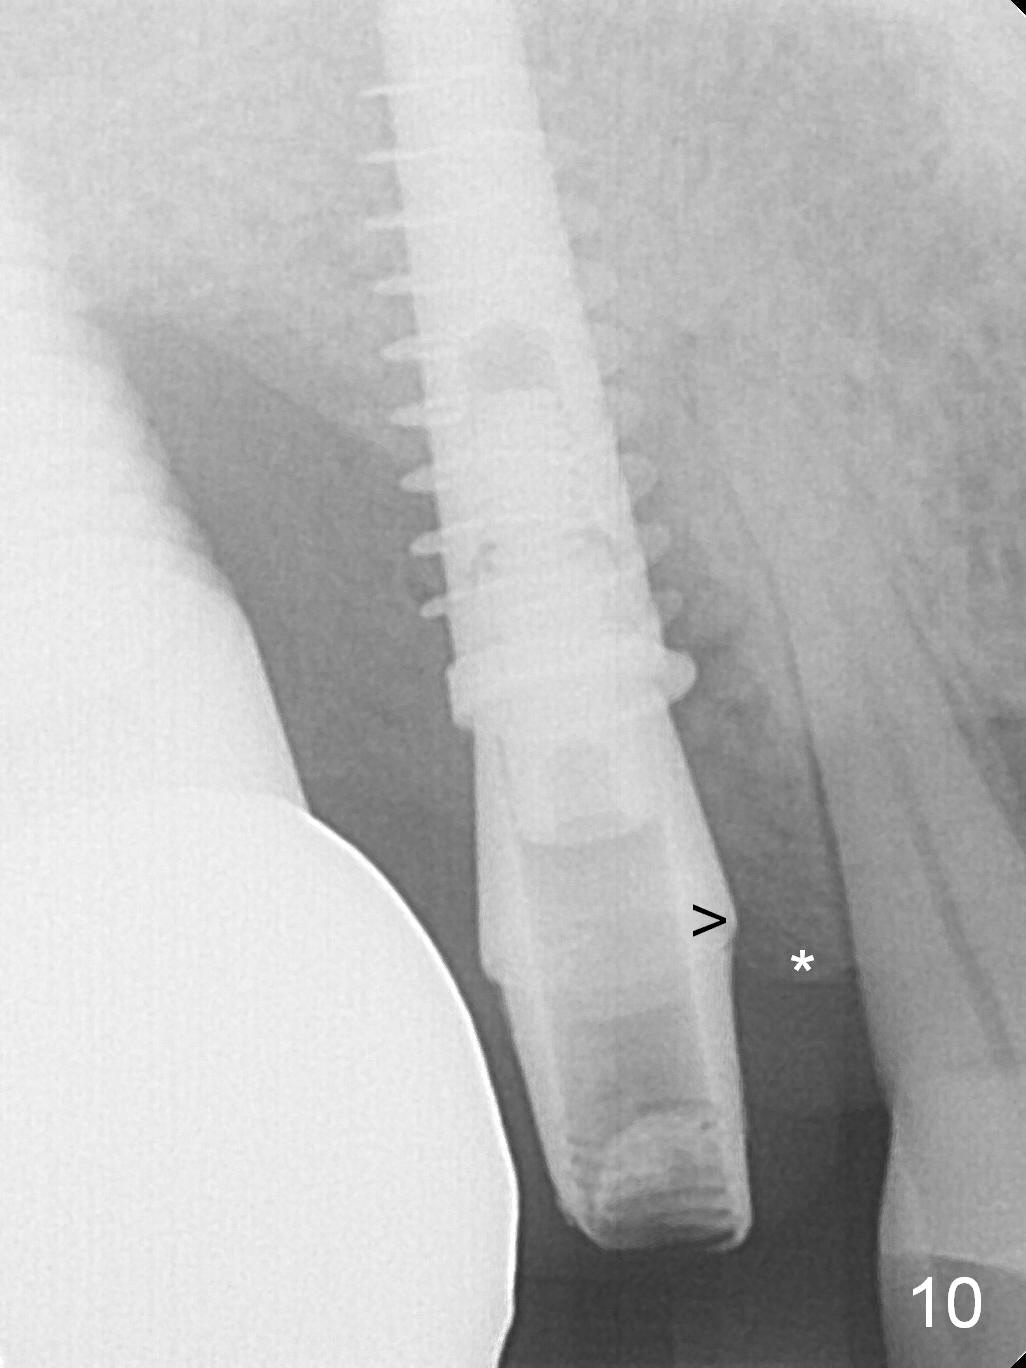

The distal papilla reforms buccally (Fig.8 *) and palatally (Fig.9) 4 months postop.  It appears that the 4 mm cuff of the pair abutment (Fig.10 >) is apical to the mesial crest (*).  The distal coronal implant threads seem to be covered by bone graft (Fig.11 <).  Therefore pair abutments with 5 mm or more cuff are required in cases of the uneven bone.   Implants have to be placed deep.  CT taken 3 months post cementation (10 months postop) shows that the implant is placed in the middle of the alveolus without apparent thread exposure.  CT taken 1 year and 8 months post cementation (Fig.13) shows that the implant is placed in the middle of the alveolus without apparent thread exposure, as compared to those at #2 and 3, which are placed buccal (B).